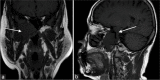

(a-c) Contrast MRI brain. A lobulated T1-weighted hypointense and T2-weighted hyperintense clival mass with moderate heterogeneous contrast enhancement, showing a honeycombing appearance (white arrows). (d) Contrast MRI brain. Extension of the mass into the foramen magnum with compression onto the brainstem. (e) Contrast MRI brain. Inferior extension with dens erosion (white arrows).